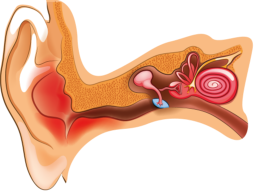

Існують різноманітні види отиту в залежності від того, яка частина вуха запалена або інфікована.

Зовнішній отит

Зовнішній отит виникає в результаті інфікування поверхні шкіри вушної раковини бактеріями або грибками. Згідно зі статистикою, приблизно 10% населення землі хоч раз в житті страждали від зовнішнього отиту.

Середній отит

Середній отит - це запальне захворювання середнього вуха, пов'язане з потраплянням в нього інфекції.